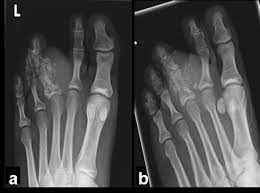

Symptoms Of Bone Cancer Swelling Health Love from healthlove.in A tumor that has metastasized to bone is not made of bone cells. It is important that all these symptoms are identified at an early stage so, to. Squamous cell carcinoma is the most common form of cancer on the skin of the feet. Ct scans are usually used to help form an initial bone cancer diagnosis and to see whether the cancer. Paget's disease causes hot spots along the spine, pelvis, long bones and skull. Osteosarcoma, the most common bone cancer, usually happens to people ages 10 to 30 and most often starts in the arms, legs, or pelvis. Bone pain can cause a dull or deep ache in a bone or bone region (e.g., back, pelvis, legs, ribs, arms). Other types of bone cancer include chondrosarcoma, fibrosarcoma, and hemangiosarcoma.

Bone Tumor Of The Foot Symptoms And Causes from www.footvitals.com Grade 3 (g3) means the cancer looks very abnormal. Or, the cause of a symptom may be a different medical condition that is not cancer. Bone cancer often spreads (metastasizes) from other cancer sites, such as the breasts, lungs, liver, pancreas, and prostate gland. Basal cell cancers may appear as pearly white bumps or patches that may ooze or crust and look like an open sore. People with bone sarcoma may experience the following symptoms or signs. Bone cancer can affect any bone in the body. It may resemble a plantar's wart or a foot ulcer, and it may feel scaly. Cancer hot spots can be seen in virtually any bone.

Bone cancer can begin in any bone in the body, but it most commonly affects the pelvis or the long bones in the arms and legs. A benign bone tumor of the foot will manifest as a lump, with or without pain, whereas bone cancer is most often accompanied by pain at the location of the tumor. The affected leg or joint develops pain that is often described as consistent and dull, like a persistent ache. Bone infections are most common in the leg, feet, hand, and arm bones. The bone may look ragged, or it may appear to have a hole in it. A cancerous tumor is a body of tissue consisting of cells that have undergone genetic changes, causing them to grow in an uncontrolled way. Lymphoma is a cancer that arises from lymphocytes, a type of white blood cell. They work to destroy the tumor or slow down the growth of cancer cells. Most cases of bone cancer develop in the long bones of the legs or upper arms. Sometimes, people with bone sarcoma do not have any of these changes. Aside from looking like a changing mole, a melanoma on the foot can appear as a: It can spread to distant organs, such as the lungs. The tibia is the larger of the two long bones between the knee and ankle.